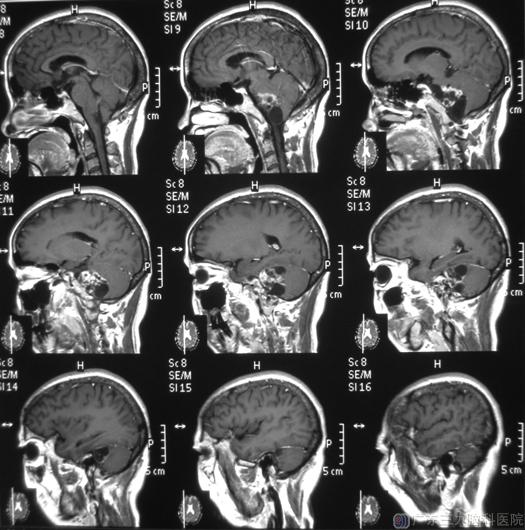

元宵节后才三天,大姨就急急忙忙地来到广东三九脑科医院,头颅MR检查提示右侧桥小脑角区占位,大小约3.5cm×4cm×4.7cm。大姨一下子傻眼了,还真是脑瘤!

综合神经外科 鲁明主任主刀,在全麻下行右侧桥小脑角区肿瘤切除术,显微镜下见淡黄色肿瘤组织位于右侧桥小脑角,电生理监测下用超声刀分块切除肿瘤,对面神经、三叉神经、舌咽神经、副神经、迷走神经及脑干等重要结构均保留完整。术后病理结果:神经鞘膜瘤。

手术前